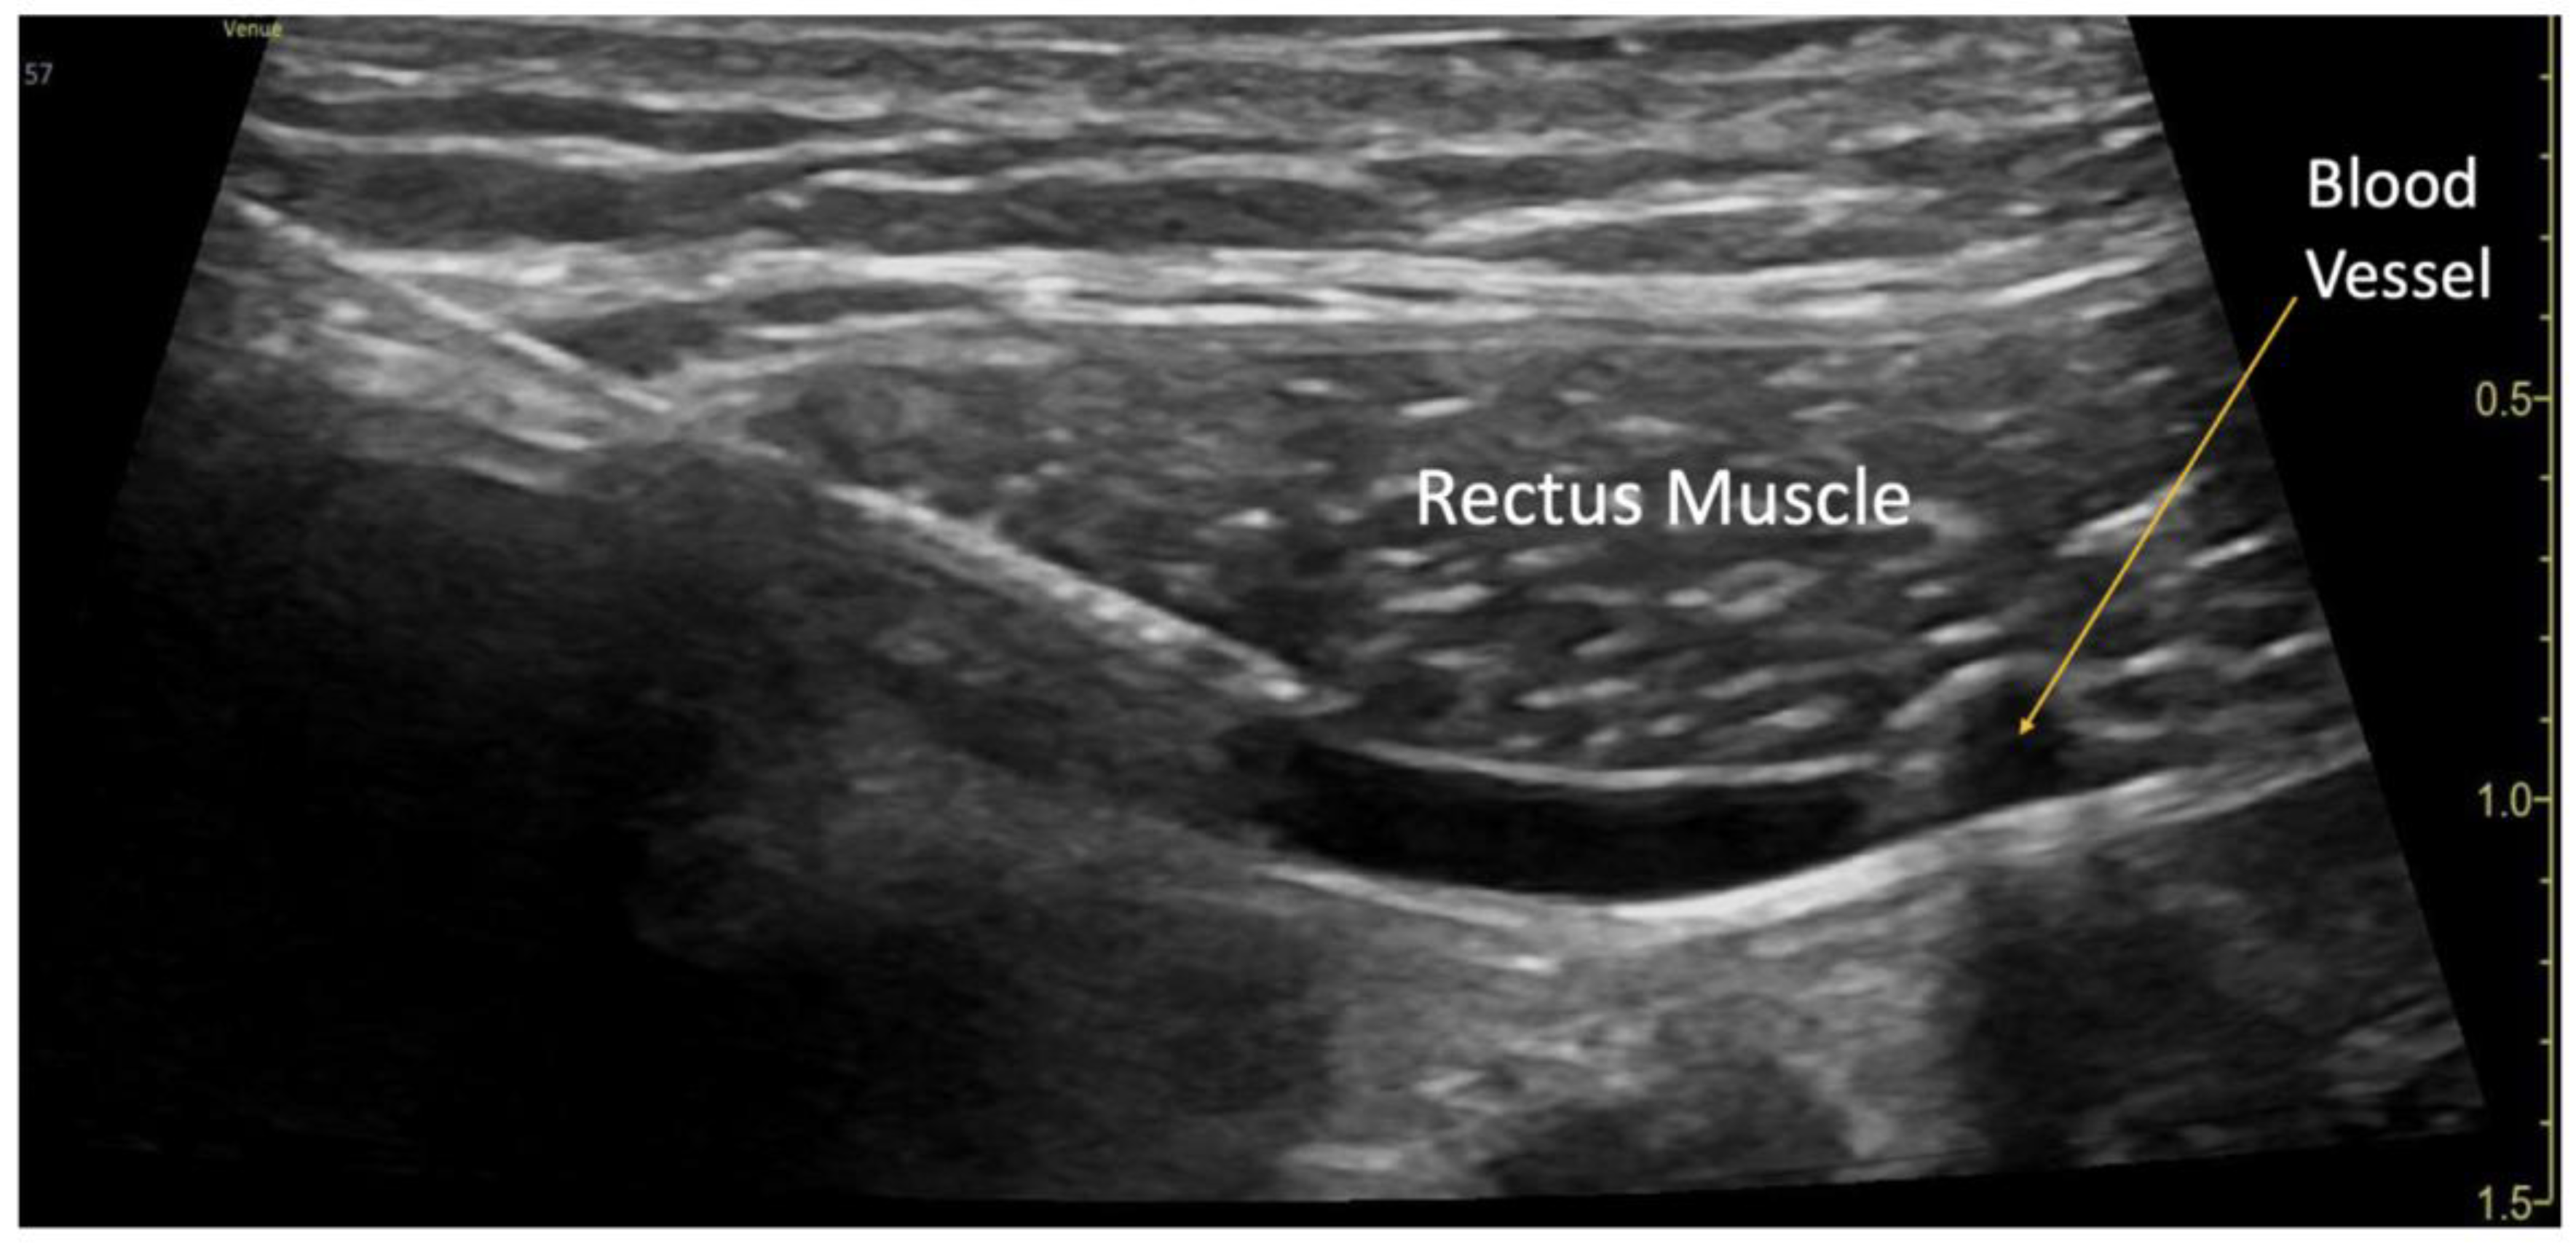

The blocks were performed while the patient was under general anesthesia, before surgery started, and after sterile preparation. A high-frequency linear transducer was positioned at the level of the umbilicus and moved laterally a few centimeters until the lateral border of the rectus muscle was visualized. An echogenic needle, 22-gauge, 50-mm Sono-TAP (Pajunck Medical Inc., Geisingen, Germany) was advanced medially from the lateral edge of the probe; final needle placement was at the lateral border of the rectus muscle, deep to the muscle, yet superficial to the posterior aspect of the rectus sheath, and not pre-peritoneal nor intraabdominal. A few milliliters (mL) of saline solution were injected until the spread of medication was visualized in the correct location (Figure 1), followed by three milliliters (mL) of local anesthetic mixture (liposomal bupivacaine 113.05 mg, bupivacaine 0.25%, 32.5 mg, and dexamethasone PF, 5mg -total volume 22 mL). This procedure was repeated at the contralateral site. Two more bilateral local anesthetic injections under the rectus muscle were performed at the level of T7 and T12 dermatomes (Figure 3a). A total of six rectus sheath blocks were performed with 22 ml of local anesthetic mixture. After the blocks were performed, medication spread behind the rectus muscle was visualized as a bulge into the space under the rectus sheath muscle from the xiphoid to the pubic symphysis (Figure 2), as described by Visoiu et al, [18] matching the incision performed (Figure 3b). The surgery then conducted was an open infrarenal abdominal aortic aneurysm repair with a Hemashift Gold 12mm graft and a 6mm limb used for aortic graft to common iliac aneurysm repair. The duration of anesthesia was 374 minutes, the aortic cross-clamp time was 95 minutes, and total blood loss for the operation was 50mL. The surgery was uneventful, and intraoperative hemodynamic stability was adequately maintained. The patient was extubated in the operating room.

Figure 1. Rectus Sheath Block Procedure. A blood vessel was visualized in the plane underneath the rectus muscle.